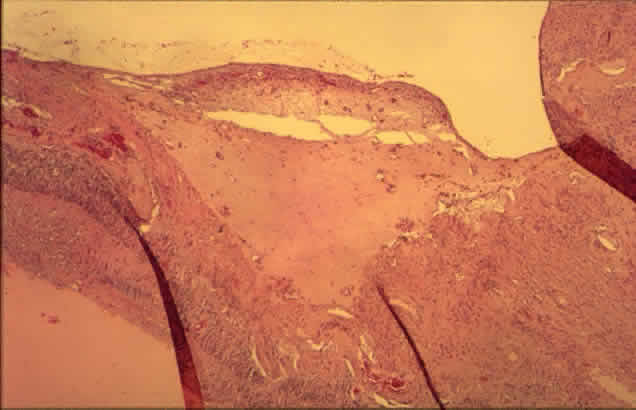

Fig. 12. Neovascularization at the disc with fibrous proliferation. The fibrovascular membrane overlies the internal limiting membrane, which is wrinkled (arrows). The retinal detachment is artifactual. (PAS, × 19.5)

Fig. 13. Neovascularization away from the disc. The fibrous tissue has contracted, imparting a triangular shape to the membrane. Active new vessels are present throughout. The dark folds are artifactual. (H&E, × 31.25)